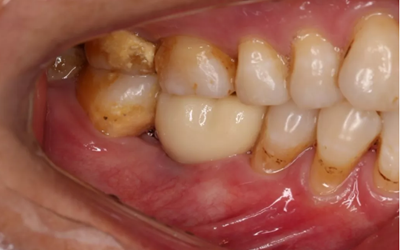

2、術(shù)前口腔內(nèi)照片

46牙烤瓷冠修復(fù),牙周紅腫,叩痛,松2度。骨吸收波及鄰牙,鄰牙牙周情況不佳,45牙松2度,47牙松1度。

(攝于2016年8月31日,反光板協(xié)助拍攝)